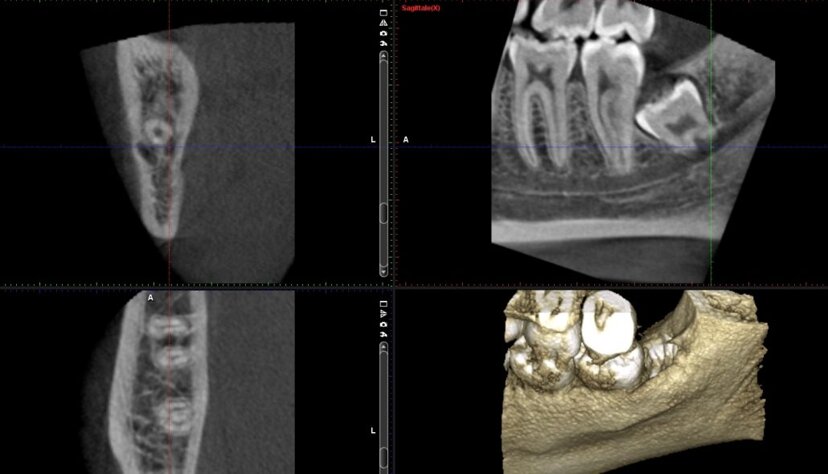

Radiografia panoramica che mostra un riassorbimento osseo alveolare diffuso secondario a parodontopatia cronica generalizzata.

La perdita ossea interessa prevalentemente le aree interprossimali, con riduzione dell’altezza crestale variabile, compatibile con una compromissione significativa del supporto parodontale.